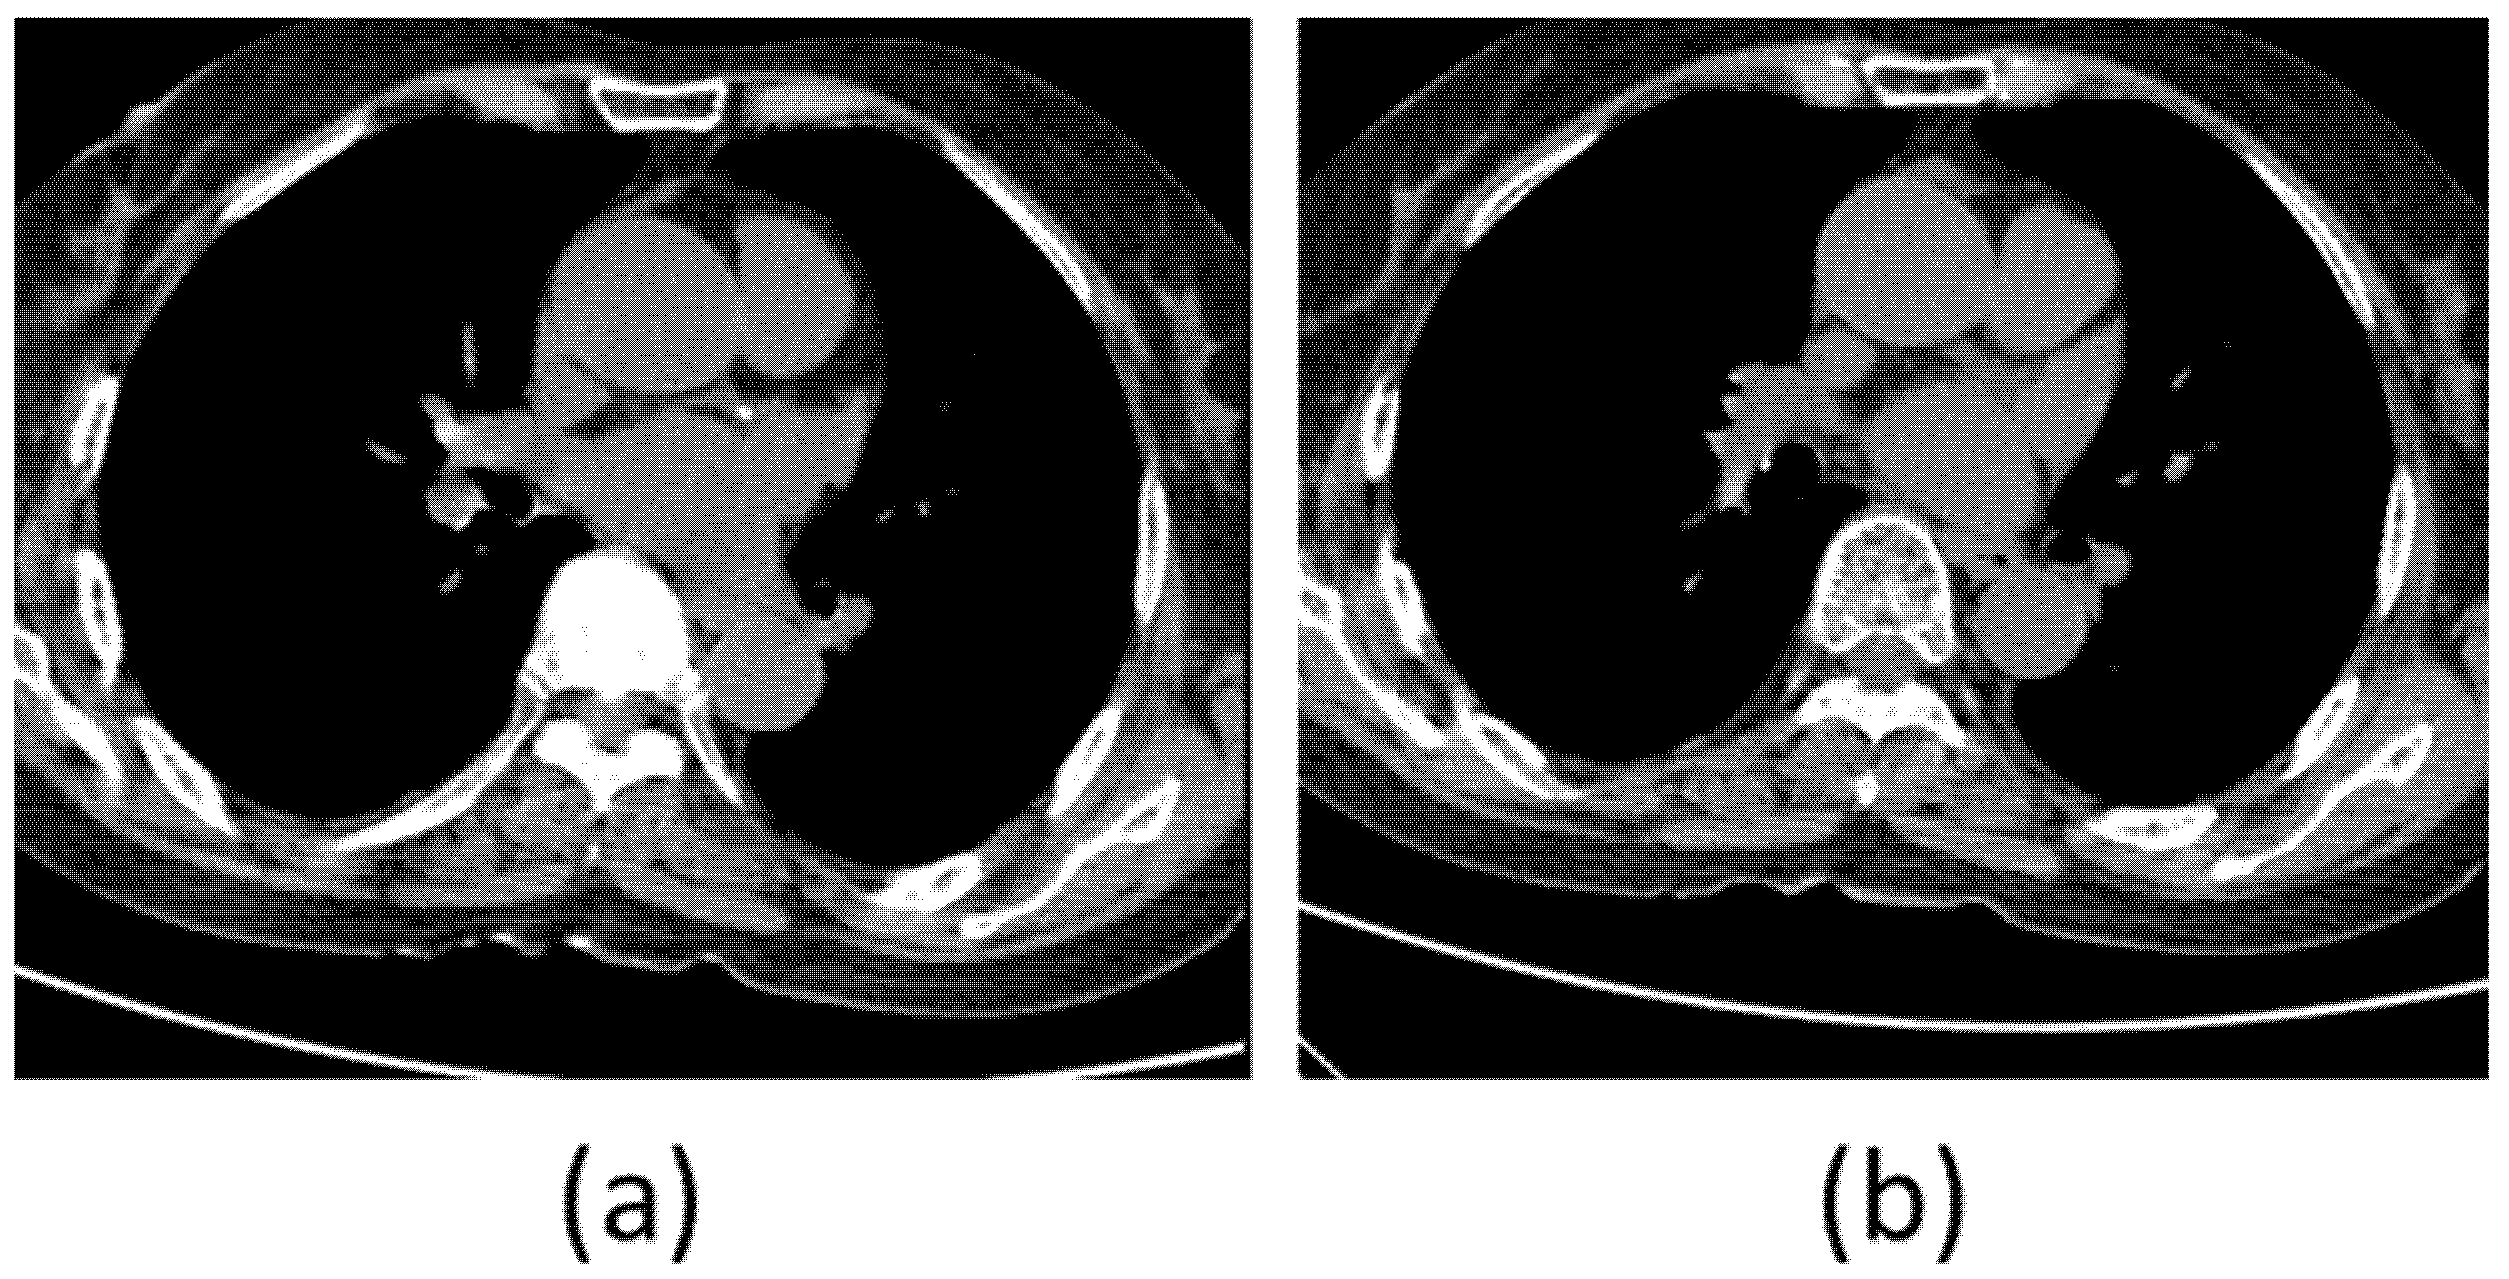

In Figure 5, the data with title beginning with ‘calcium’ is the data with calcium in the coronary arteries, while the data with title starting with ‘no_calcium’ is the normal data, in which calcification in the coronary arteries has not progressed.

Figure 5.

(a) Original coronary artery calcium score CT image without calcification, (b) Original coronary artery calcium score CT image with calcification.